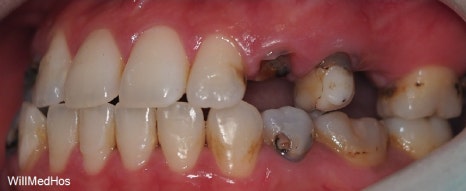

먼저 구강 사진 부터 보도록 하겠습니다.

이미 충치들과 염증으로 인해 치관을 다 없어지고 잔존 뿌리들만 겨우 남아있는 상태들의 치아들

염증으로 인하여 살리기 힘든 치아들도 다수 있었습니다

나이가 젊으신 분인만큼 최대한 살릴 수 있는 치아들은 살리고 임플란트 필요 치아들을 치료하는 방향으로 계획을 잡았습니다.